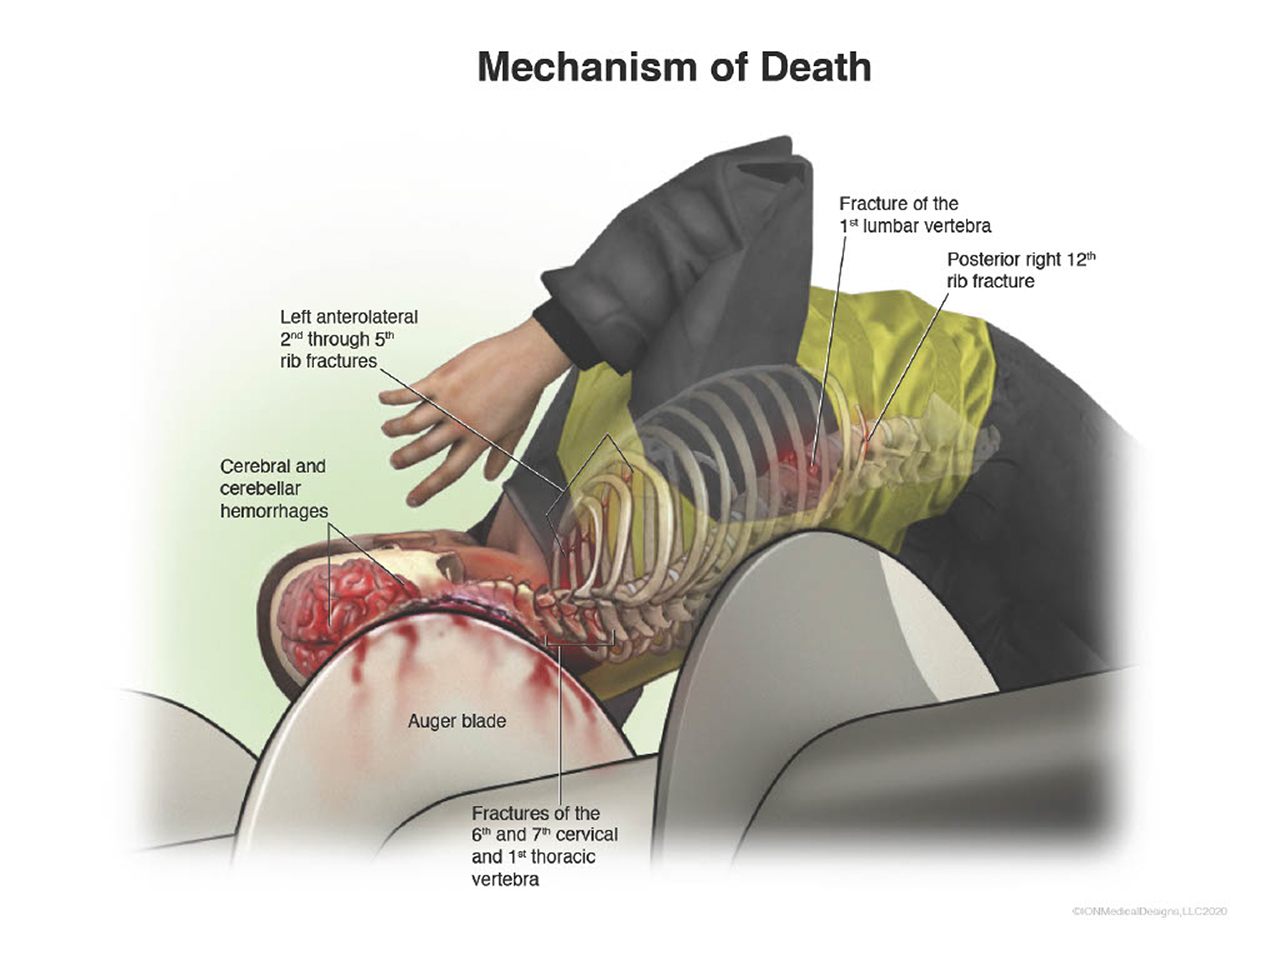

I worked on along nine law firms and two doctors on a mass shooting case not realizing that the majority of the victims were children until after agreeing to work on it. I struggled with this a lot but came to the realization that these children needed to be represented and have a voice at their bench trial. I ended up assisting the attorneys to secure a 230 million dollar verdict against the United States Government!

I work a lot with attorneys to create medical demonstrative aids for insurance adjusters, mediations and trials. These medical demonstratives help to secure settlements for severely injured and families of decedents.